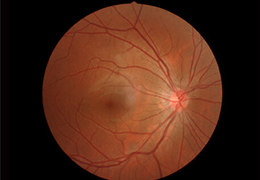

成像智能。

Eclipse 成像智能功能提供强大的处理能力和最佳质量的影像,同时减少质量错误并提高剂量效率。

凭借 AI、专有算法和先进的影像处理能力,提供出色的影像质量和无与伦比的诊断信心。